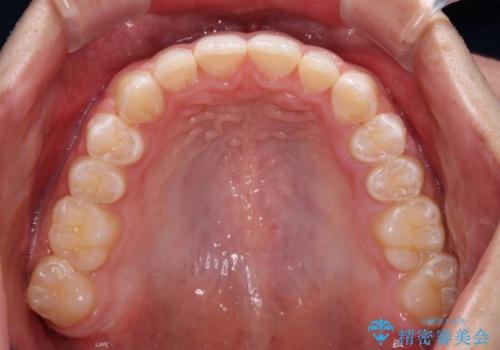

下顎前歯が全て隠れてしまうほどの深い咬合で、左右の奥歯は1歯対1歯で咬み合う状態でした。

前方に移動している上顎臼歯を補助装置にて遠心移動させることで1歯対2歯の臼歯咬合を目指し、同時に深い咬合を改善していくこととしました。

このような咬み合わせの場合、治療期間は2年以上がかかることが一般的で、3年程度かかることもありえるケースです。

強く深い咬み合わせにより下顎装置は頻繁に脱離するため、治療期間が長くなりますが、予定通りに終了させることができました。